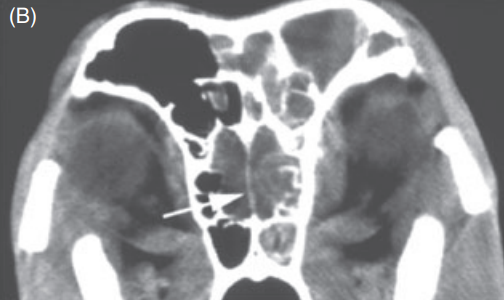

CT상에서 두개골이 융해된 양상을 보이는 등 악성 종양의 전형적인 특징들이 보이게 된다.

또한 전두엽까지 침습한 양상의 악성종양의 조건을 모두 갖추고 있다.